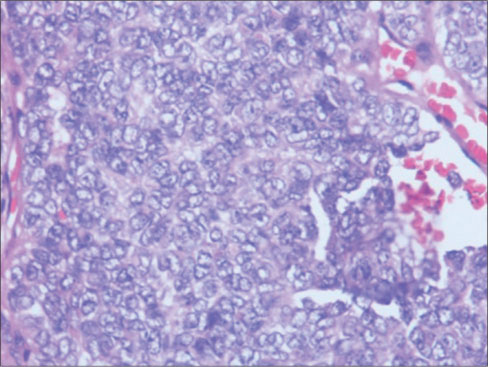

A 56-year-old gentleman presented with painless progressive swelling on the left side of the abdomen for 6 months, associated with skin ulceration and discharge without any constitutional symptoms. Contrast-enhanced computed tomography (CECT) of the abdomen showed 166 mm × 123 mm × 45 mm heterogeneously enhancing anterior abdominal mass in the left lumbar region, with loss of fat plane between the mass and underlying muscle. The lesion was extending up to the skin with focal areas of ulceration, without intraperitoneal or retroperitoneal extension. CECT of the chest revealed well-defined heterogeneously enhancing lesions in the left lower lobe suggestive of metastases. Biopsy from the primary lesion showed medium-sized neoplastic cells arranged in sheets [Figure 1] with scanty cytoplasm [Figure 2] and round-to-oval nuclei with inconspicuous nucleoli consistent with poorly differentiated malignancy. Immunohistochemistry (IHC) showed leukocyte common antigen-negative, Melan A-negative, pancytokeratin dot-like positive [Figure 3], CD34-negative, cytokeratin 20 (CK20) dot-like positivity [Figure 4], CD 56-positive, CD 117-negative, and chromogranin-negative. Morphology with IHC correlation was suggestive of MCC. Brain and bone scans were normal.

| Figure 2: Monotonous population of cells having scanty cytoplasm, round vesicular nucleus with finelygranular chromatin with marginated nucleoli, (H and E × 400)